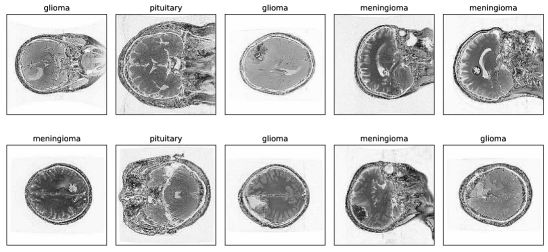

The preprocessed images are sharper, brighter, and have more detectable details than the original images, making them appropriate for driving into the model and achieving greater performance than existing works. Figure 5 illustrates the image preprocessing steps for brain tumor types, including glioma, meningioma, and pituitary. The top section of the figure (a,b,c) shows the images before preprocessing, while the bottom section (d,e,f) displays the images after the preprocessing steps have been applied.

Refer to caption

(a) Before (glioma)

(b) Before (meningioma)

(c) Before (pituitary)

(d) After (glioma)

(e) After (meningioma)

(f) After (pituitary)

Figure 5: Brain glioma, meningioma and pituitary image before and after image preprocessing